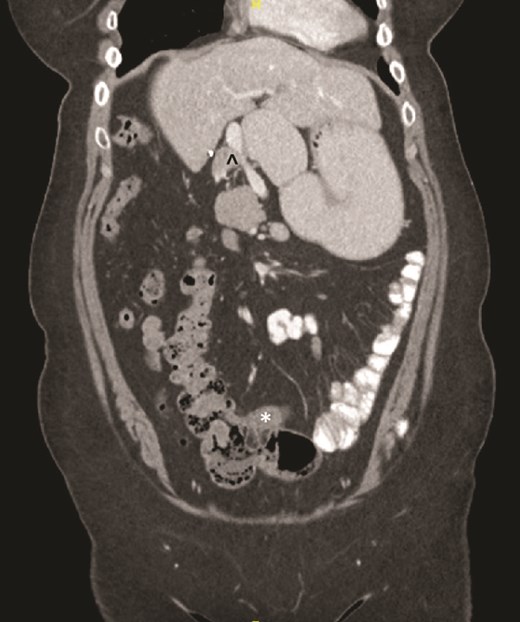

On examination, the abdomen was soft but mildly distended. Bowel sounds were heard, and the epigastrium was mildly tender. Standard bloodwork was normal. Review of an abdominal computerized tomography (CT) scan from 4 years prior showed congenital malrotation of the bowel, with the small bowel to the left of the midline and colon entirely to the right (Fig. 1). There was partial agenesis of the dorsal pancreas (Fig. 2), azygous continuation of the inferior vena cava (IVC), a retroaortic and retrocrural left renal vein, and an unremarkable spleen alongside some splenules. The PV traversed anterior to the first part of the duodenum (Fig. 3). There was relative narrowing of the distal stomach and the duodenum was nondilated.

Terminal ileum (*) seen entering cecum with completely right-sided colon and left-sided small bowel visible. PDPV also seen (^) causing partial duodenal obstruction.